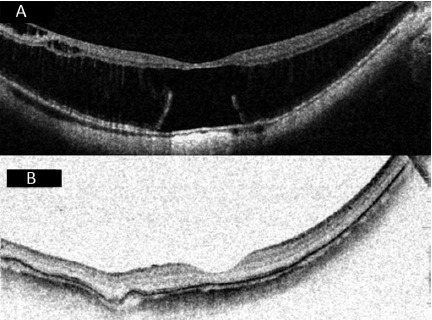

以下为典型患者的术前及术后眼底 OCT 以及 MRI 结果(图 2-8)。

8.png

图 7 A 为后巩膜葡萄肿黄斑脱离合并裂孔患者术前 OCT,视网膜前膜表现为中心凹外的切向牵引力;B 为同一只眼术后 2 年,视网膜 - 脉络膜 - 巩膜在扣带处完全变平,黄斑脱离恢复且无切向牵引力(扣带组)